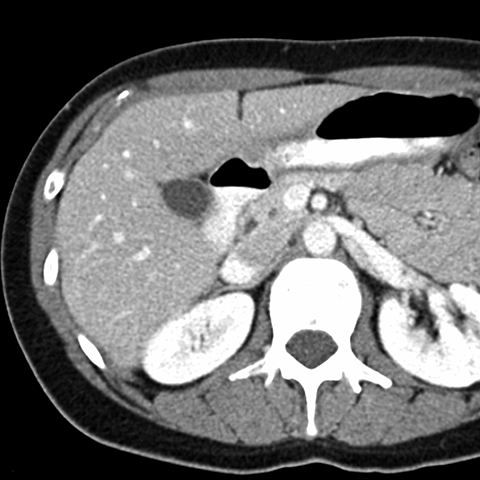

Normal Liver, CT ( axial ) [8 of 9]